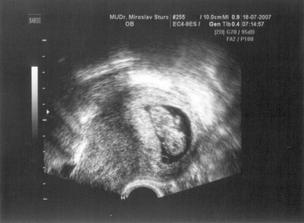

18.7 UTZ, kde nám krásně bilo srdíčko